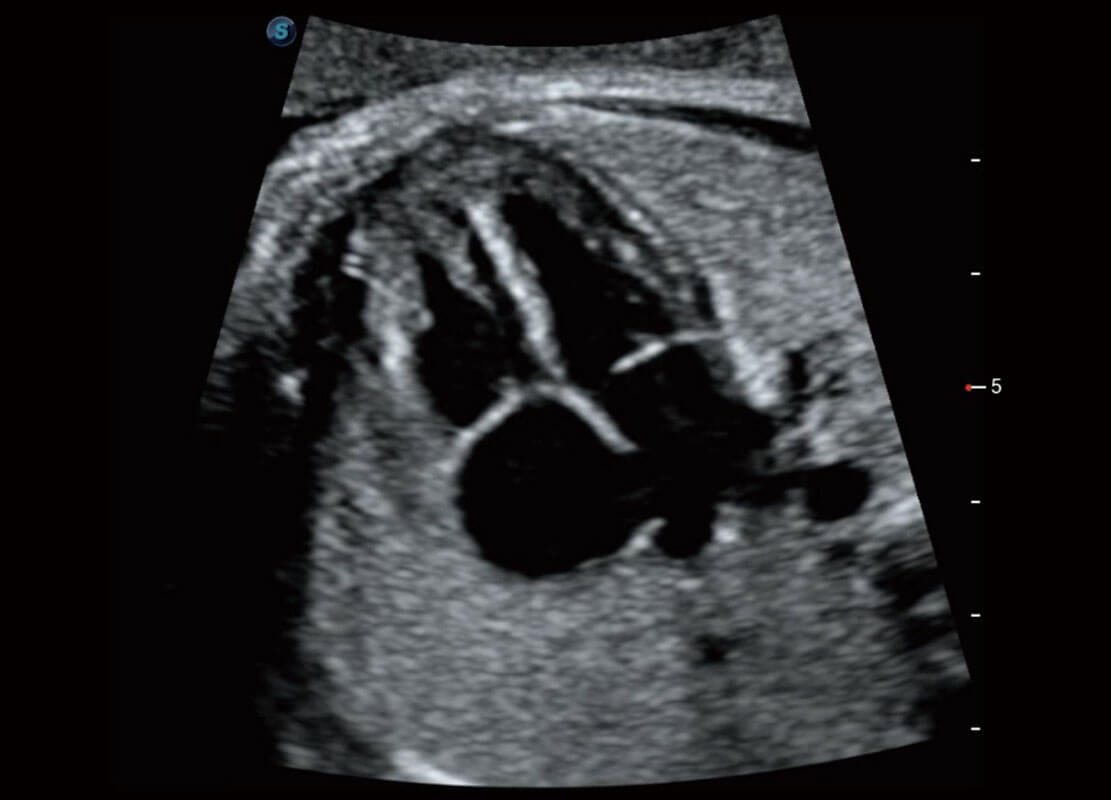

P60优异的图像质量搭载专科探头,在妇科基础疾病的诊断、卵泡生长的监测、输卵管通畅情况的判别等方面为您提供生殖应用方案。

腔内妇科-宫腔分离

腔内妇科-卵巢